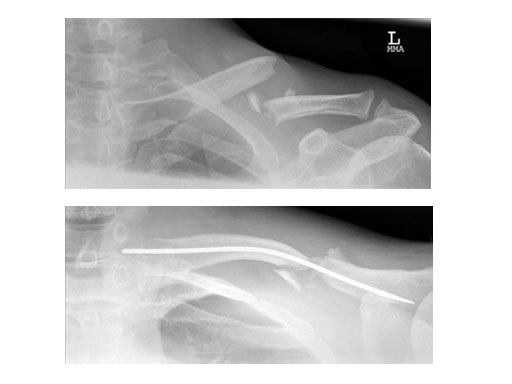

Case 2: 51 years, male, hit by tree